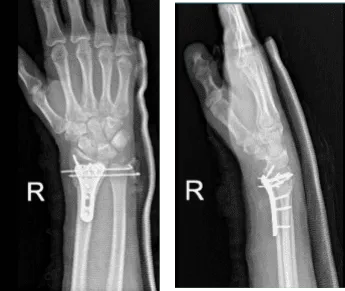

4th week post operative, considering the wires were poking under skin and imminent to break it, we decided to remove the wires and long arm splint to continue. Xray result reviewed.

Right wrist X-ray 3 or more views-4th week post operative